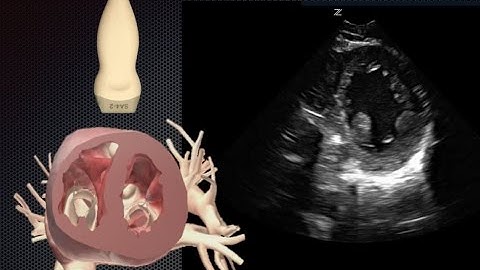

How To: Parasternal Short Axis View, Echocardiography 3D Video